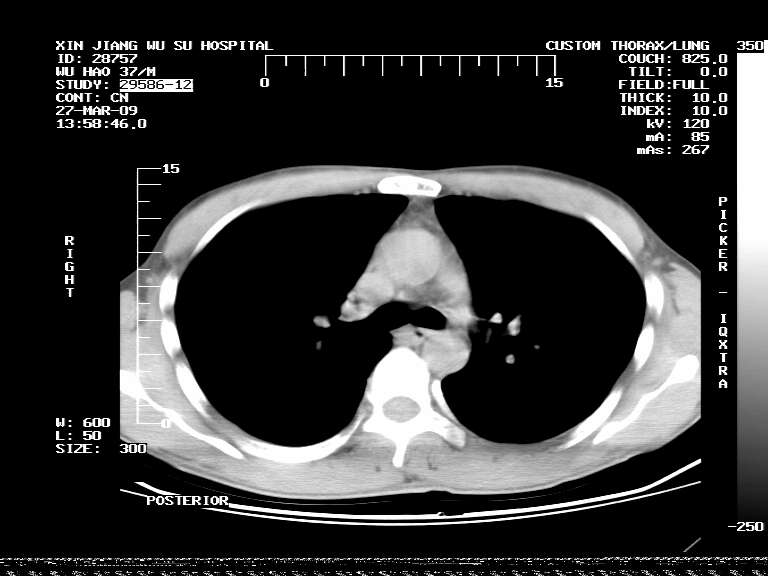

男,37岁,体检胸透发现阴影。

患者体检发现 无症状 左肺下叶占位,边缘模糊,可见血管聚束、分叶、胸膜牵拉,增强呈不均匀性强化。 首先考虑左肺下叶周围型肺癌,建议穿刺活检。

左肺下叶见一结节病变,边缘欠清不光滑,与胸膜粘连且胸膜局限性增厚,注药后呈环形强化,动脉期壁呈明显点环状强化,静脉期壁强化减低,中心密度低无强化,灶周无明显的卫星灶和水肿区(晕征)---考虑周围性肺癌,不除外感染性病变,建议穿刺活检。

左肺下叶软组织病灶,密度较高,内见点状钙化,其周围见子灶,邻近胸膜扁平样增厚.c+病灶强化明显,中心强化弱.诊断:左肺下叶结核瘤.

左肺下叶大片实变影,内靠胸膜见不规则更高密度结节灶,边缘强化,相邻胸膜增厚,胸膜下脂肪线存在。考虑炎症,结核可能。